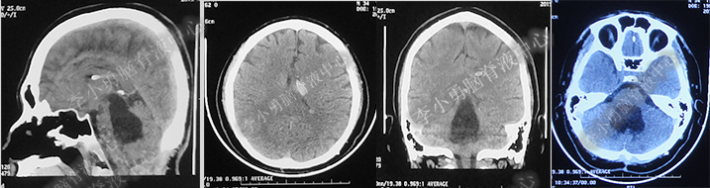

术后7天(2016年5月18日),症状有所缓解,复查头部MRI(图-2)幕上脑室较术前缩小,但是“四脑室仍扩张”,医生认为 “正常”于术后8天(2016年5月19日)出院。

图-2:2016年5月18日头部MRI

图-3:2016年9月26日头部MRI

第1次内镜术后330余天即11个月(2017年4月),又开始出现头晕症状并逐渐加重。2017年6月13日(第1次内镜术后367天),行头部MRI(图-4)检查显示全脑室系统扩大。

图-4:2017年6月13日头部MRI